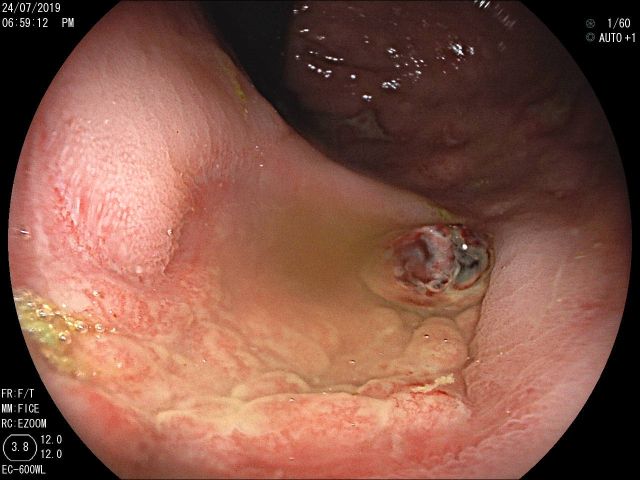

Refractory tracheoesophageal fistula management with Amplatzer Occluder placement

Menção Honrosa - Fotografia